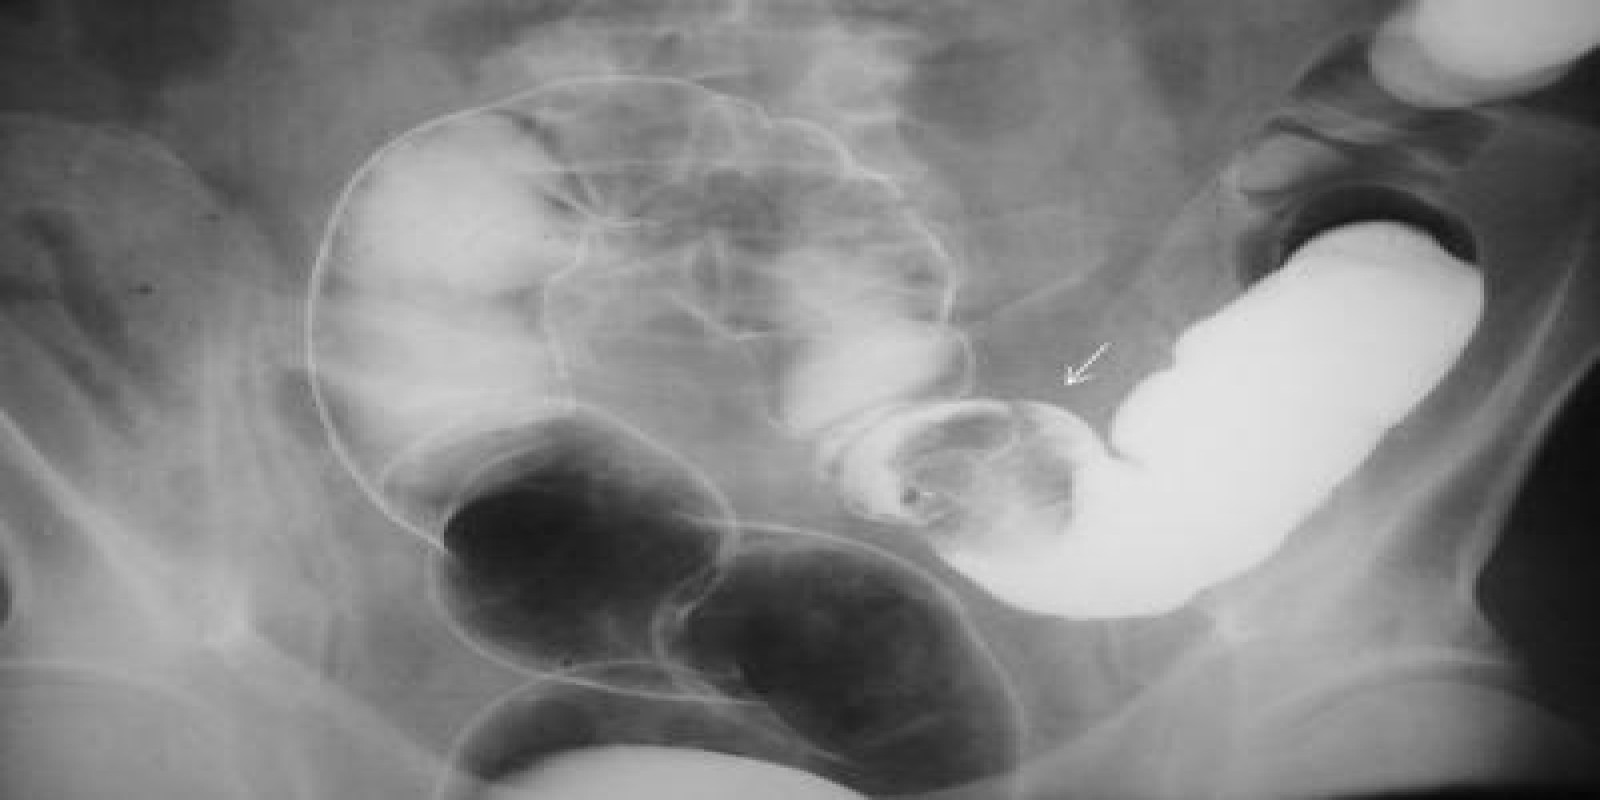

Caso Código 126A de Pólipos do Cólon

Cod.: 126A